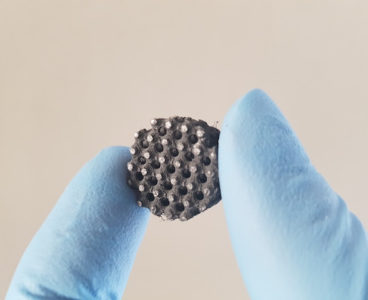

Rice bioengineers 3D-print implants to seed multiple layers of tissue

Who ever said bioengineers can’t get their groove on? The Rice University team led by Antonios Mikos says otherwise with its development of a groovy method to seed sophisticated, 3D-printed tissue-engineering scaffolds with living cells to help heal injuries. The researchers are literally carving grooves into plastic threads used to build the scaffolds. The grooves…